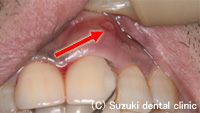

| 今回原因が歯ぐき(歯周病)であるのでポケットより消毒液で消毒すると噴水のように出てくる |